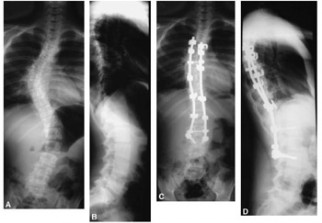

Pas moins de 30 interventions chirurgicales sur scoliose ont été effectuées, depuis mai 2014, sur la table artisanale fabriquée à l’EHS «Dr Benzerdjeb» d’Ain Temouchent, a-t-on appris du docteur Benmansour du service de chirurgie infantile (CCI).

Adaptée aux interventions chirurgicales d’enfants atteints de scoliose ou déformation de la colonne vertébrale, cette table, appelée «Table de Cotrel», fabriquée dans les ateliers de l’établissement hospitalier «Dr Benzerdjeb», a permis d’opérer 30 malades atteints de scoliose, a-t-on indiqué, en marge de la dernière visite du ministre de la Santé, de la Population et de la Réforme hospitalière, dans la wilaya. Cet équipement revenant à 12 millions DA à l’importation, a été fabriqué localement pour un coût de 200.000 DA, a souligné à l'APS le Dr Benmansour, ajoutant qu’il permet un gain de temps d’une heure et demie lors de la préparation du malade pour l’intervention.

L’EHS «Dr Benzerdjeb» a effectué, depuis 2012, année de l’introduction de ces interventions grâce à des actions de formation et d’échanges d’expériences avec des établissements étrangers, une centaine d’opérations sur scoliose d’enfants et adultes (d’origine neuromusculaires).

Ces interventions, programmées dans le cadre de la prise en charge de la scoliose, qui reviennent entre 70.000 et 90.000 Euros à l’étranger, ne coûtent qu’entre 2.000 et 3000 Euros à l’EHS Dr Benzerdjeb, a-t-on indiqué.